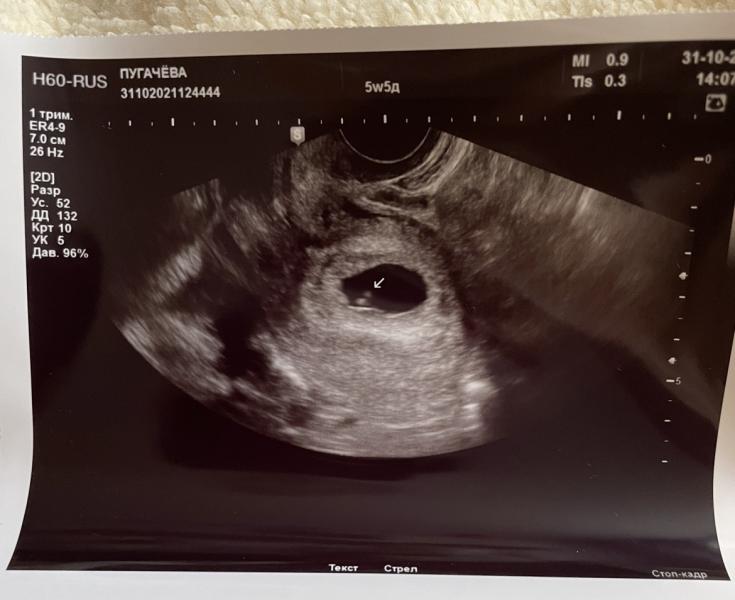

Итак, 31 октября 5 недель 5 дней:

Размер плодного яйца 16мм, КТР 5мм, желточный мешок до 3мм, сердцебиение до 106 уд/мин ! 😳 (по сердцебиению сказали вообще 6 недель 1 день, как так то 🤷🏻♀️ может ранняя овуляция все таки?), я не ожидала услышать ❤️ так рано 😁

И, не ожидала услышать, что у меня - ❗️ретрохориальная гематома 24x6x7 мм.. (не кровит) это маленькая или большая считается?

На снимке с эмбрионом направил стрелочку на него)